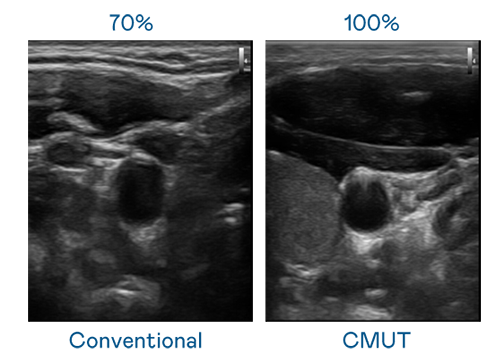

CMUT 技术是一种用电容式微机电元件来产生超音波讯号的技术。与传统 PZT 压电式技术相比,CMUT 频宽增加 30%,更宽频的超音波讯号让影像解析度大幅提升,是实现高影像品质医疗超音波扫描、促进精准医疗发展的关键技术。

大频宽带来超清晰影像

超音波影像的解析度高低,首先取决于探头能发出的讯号频宽。梦之城 CMUT 可提供高清晰的超音波讯号,提供高频宽、高灵敏度、影像纹理细节更高的超音波影像,协助医护人员缩短影像判读时间及利用精准的医疗影像进行诊断。